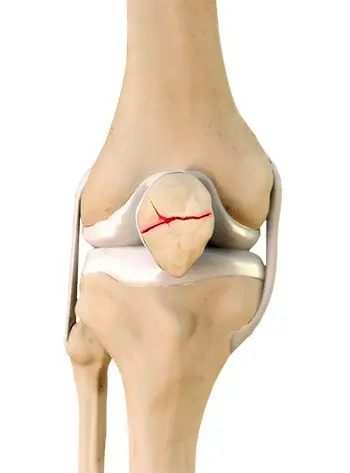

Patella Fracture